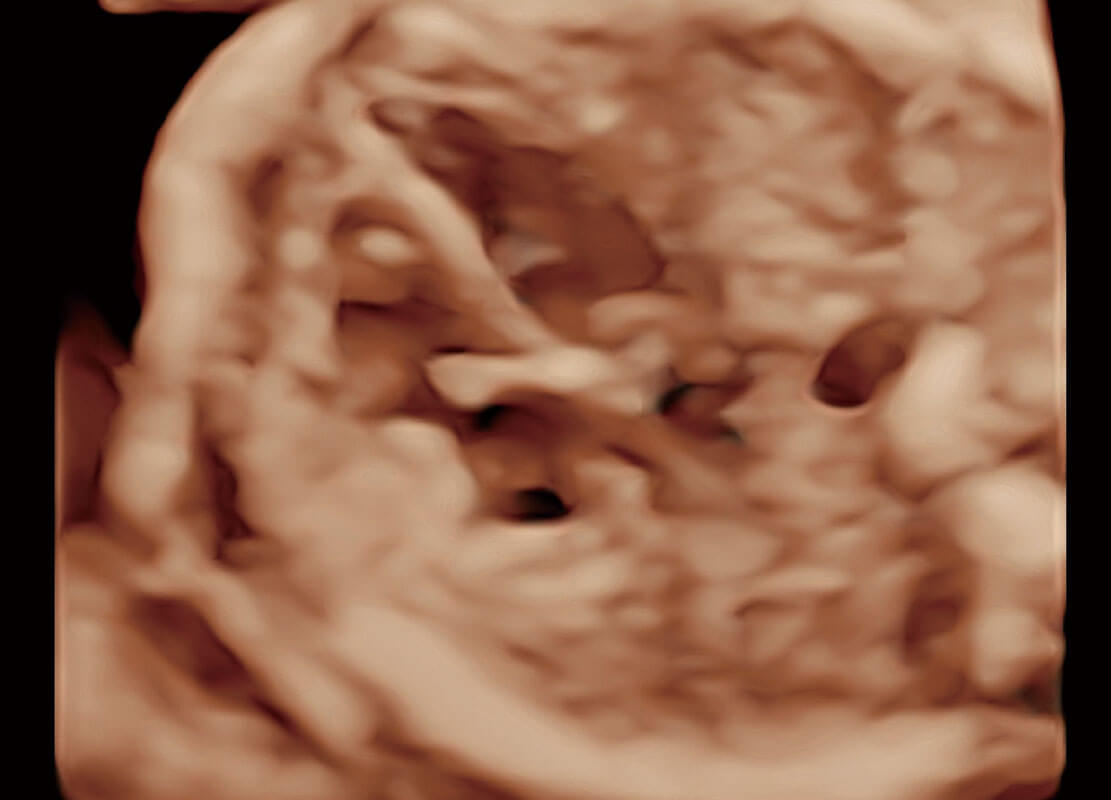

高分辨率容积成像-早孕胎儿

光影成像-孕囊